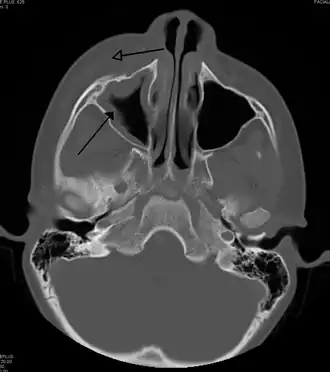

![]() Celulitis periorbitaria secundaria a infección dental (con presencia de sinusitis maxilar) | ||

La celulitis periorbitaria debe diferenciarse principalmente de la celulitis orbitaria, debido a que la segunda requiere un manejo hospitalizado con tratamiento antibiótico endovenoso y, en algunos casos, drenaje quirúrgico. En general, los pacientes con celulitis periorbitaria presentan una lesión eritematosa con bordes difusos, con aumento de la temperatura local, fiebre, dolor e inyección conjuntival con epífora. En contraste con una celulitis orbitaria, no tiene compromiso ocular (indemnidad de los movimientos oculares, ausencia de dolor y sin compromiso de la agudeza visual). En caso de presentarse alguno de estos síntomas, es necesario realizar una tomografía computarizada para descartar compromiso postseptal.[4]